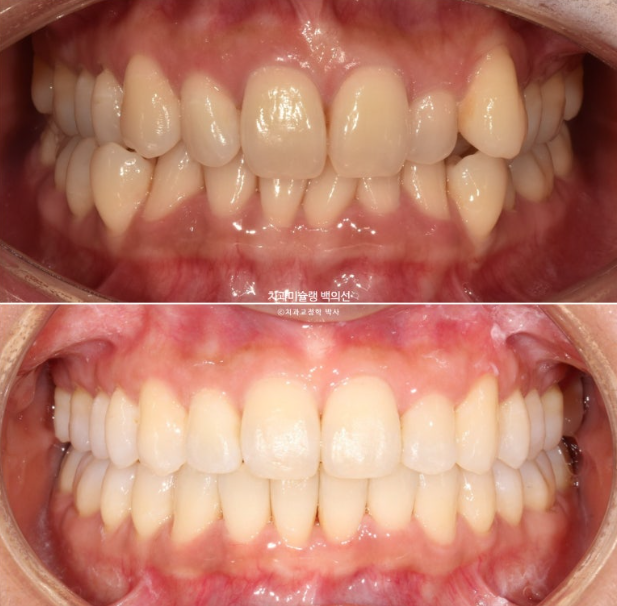

1년 전, 교정치료를 위해 온 환자분입니다.

24.08

환자분이 고치고 싶은 것은 덧니입니다.

송곳니와 작은어금니 덧니가 보이며 작은어금니가 거꾸로 물리는 반대교합도 보입니다.

앞니 중심선은 약 2mm 어긋나 있습니다.

위 앞니가 아래앞니를 많이 덮어 깊게 물리는 과개교합도 있습니다.

덧니로 배열에서 튀어나와있는 치아들은 잇몸이 내려가 있습니다.

다행히 큰어금니 교합은 좋은 편